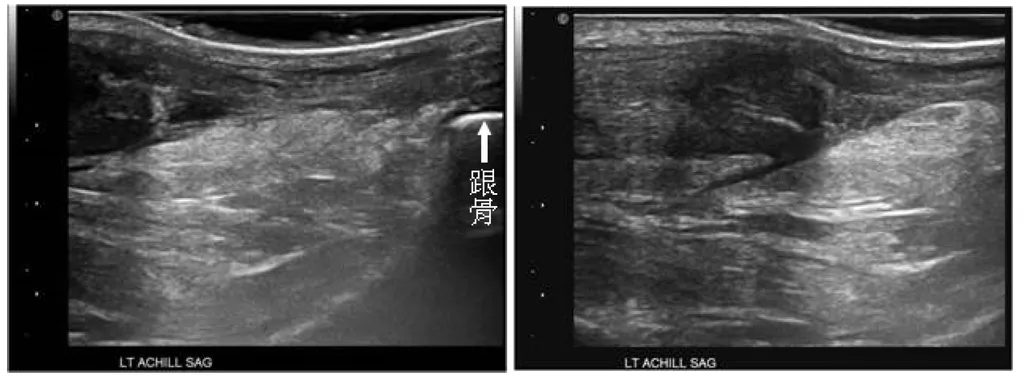

57歲女士主訴下樓梯時,突然左腳後跟劇烈疼痛,隔天至骨科門診,接受腳後跟超音波檢查矢狀切面如圖, 最可能之診斷為何?

本題的解題核心在於辨識超音波影像中阿基里斯腱的完整性,圖片清楚顯示腱體有明顯的斷裂缺損,且有液體或血腫填充。